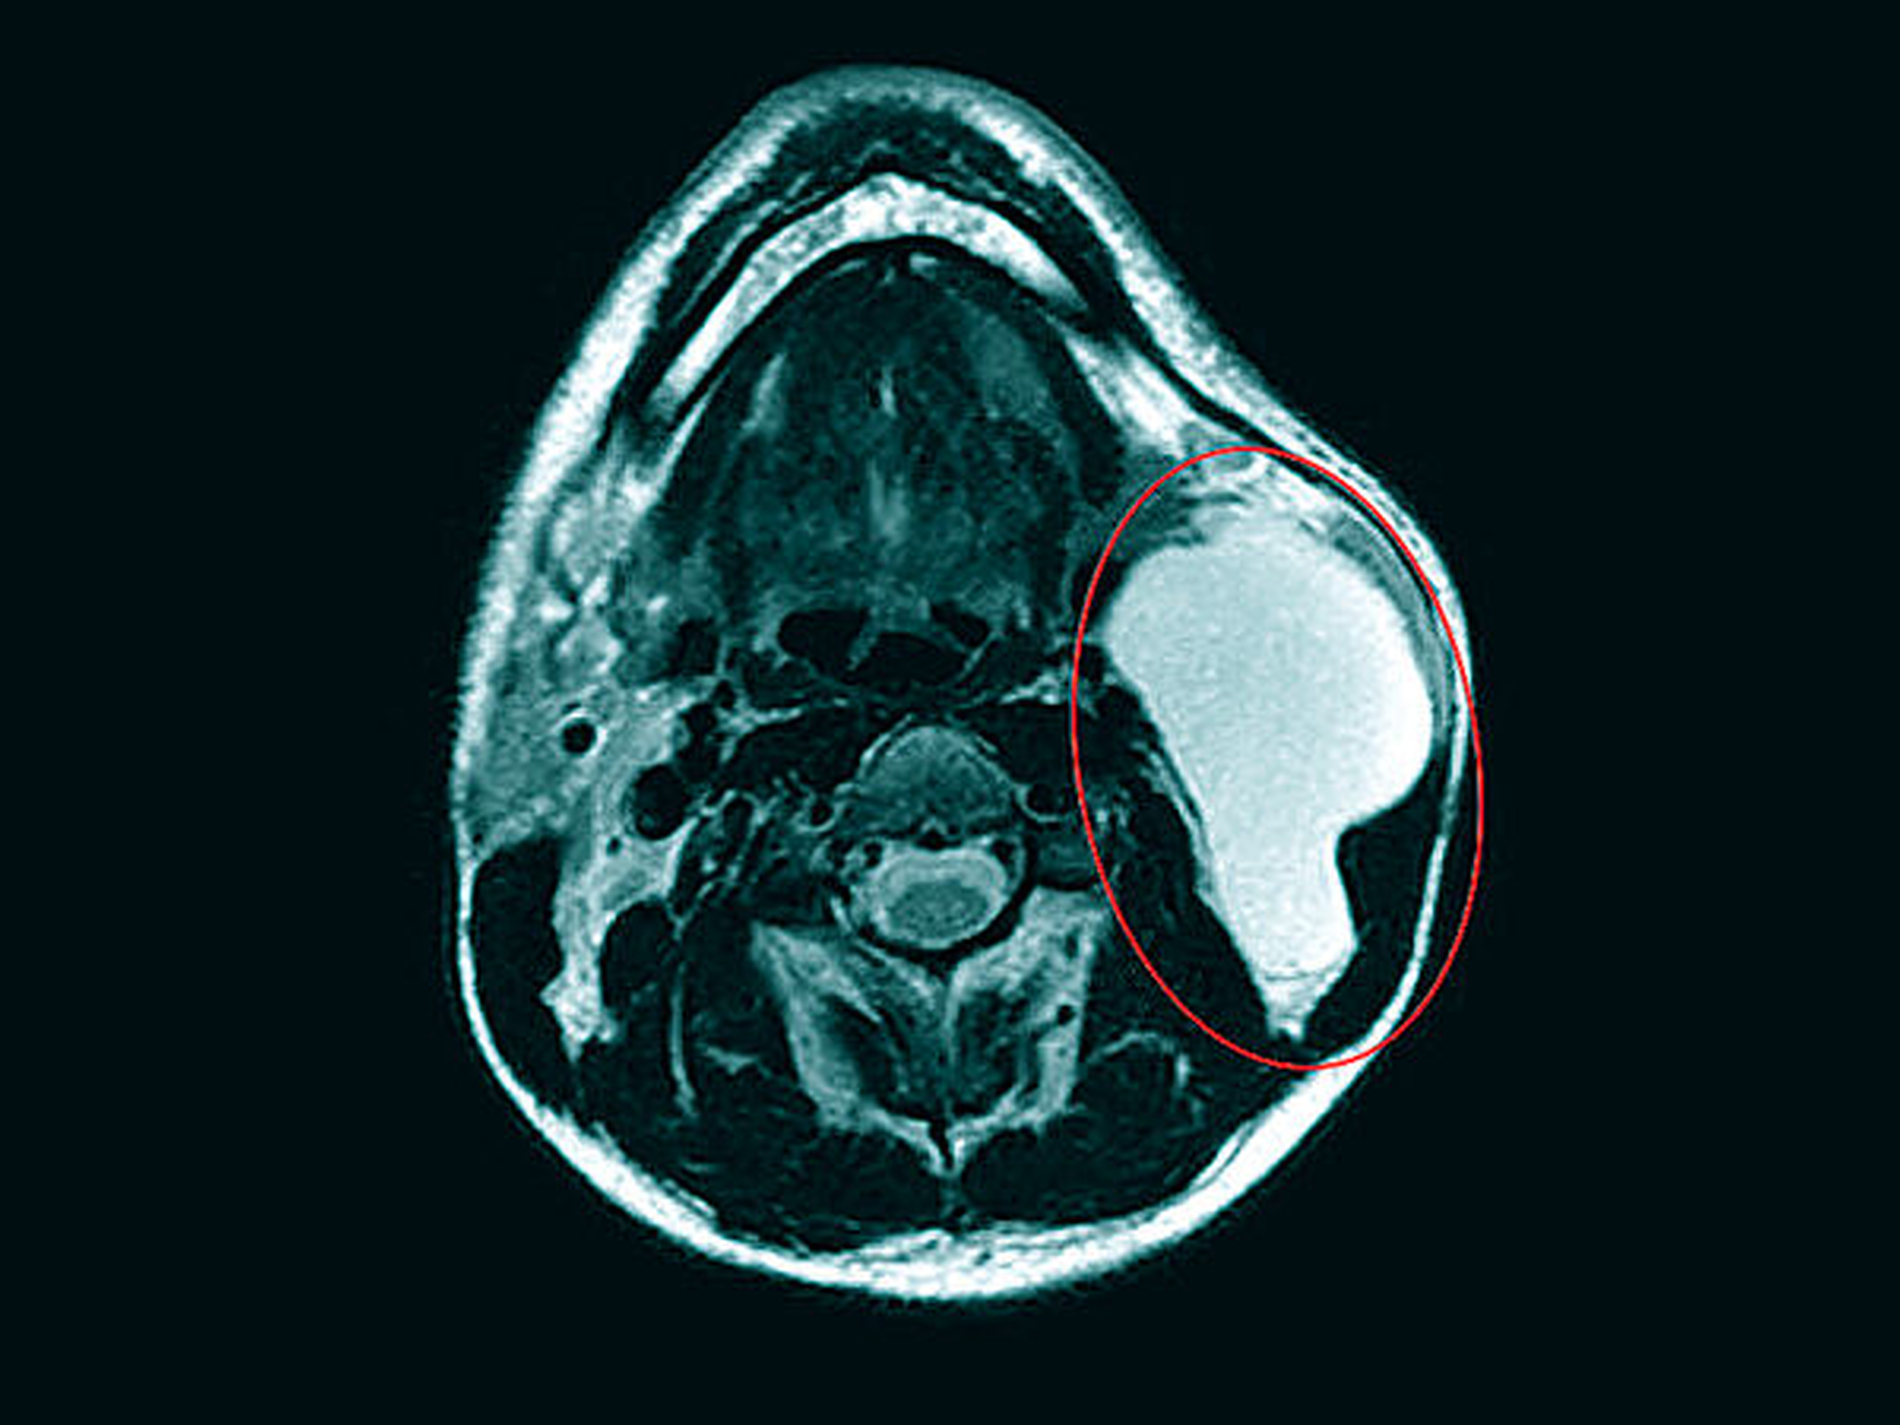

Zur weiteren Abklärung wurde eine Magnetresonanz-Untersuchung initiiert. Es zeigte sich eine glatt berandete, T2-hyperintense Raumforderung zervikal links auf Höhe der Epiglottis. Eine Infiltration der benachbarten Strukturen war nicht ersichtlich (Abbildungen 2 bis 4).